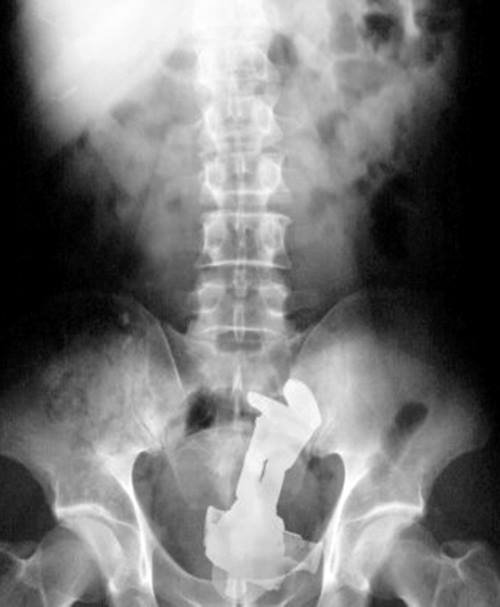

Vibrador:

Como se não bastasse um vibrador, ainda tentou retirar com uma pinça e acabou engolindo a pinça também, que coisa horrível.